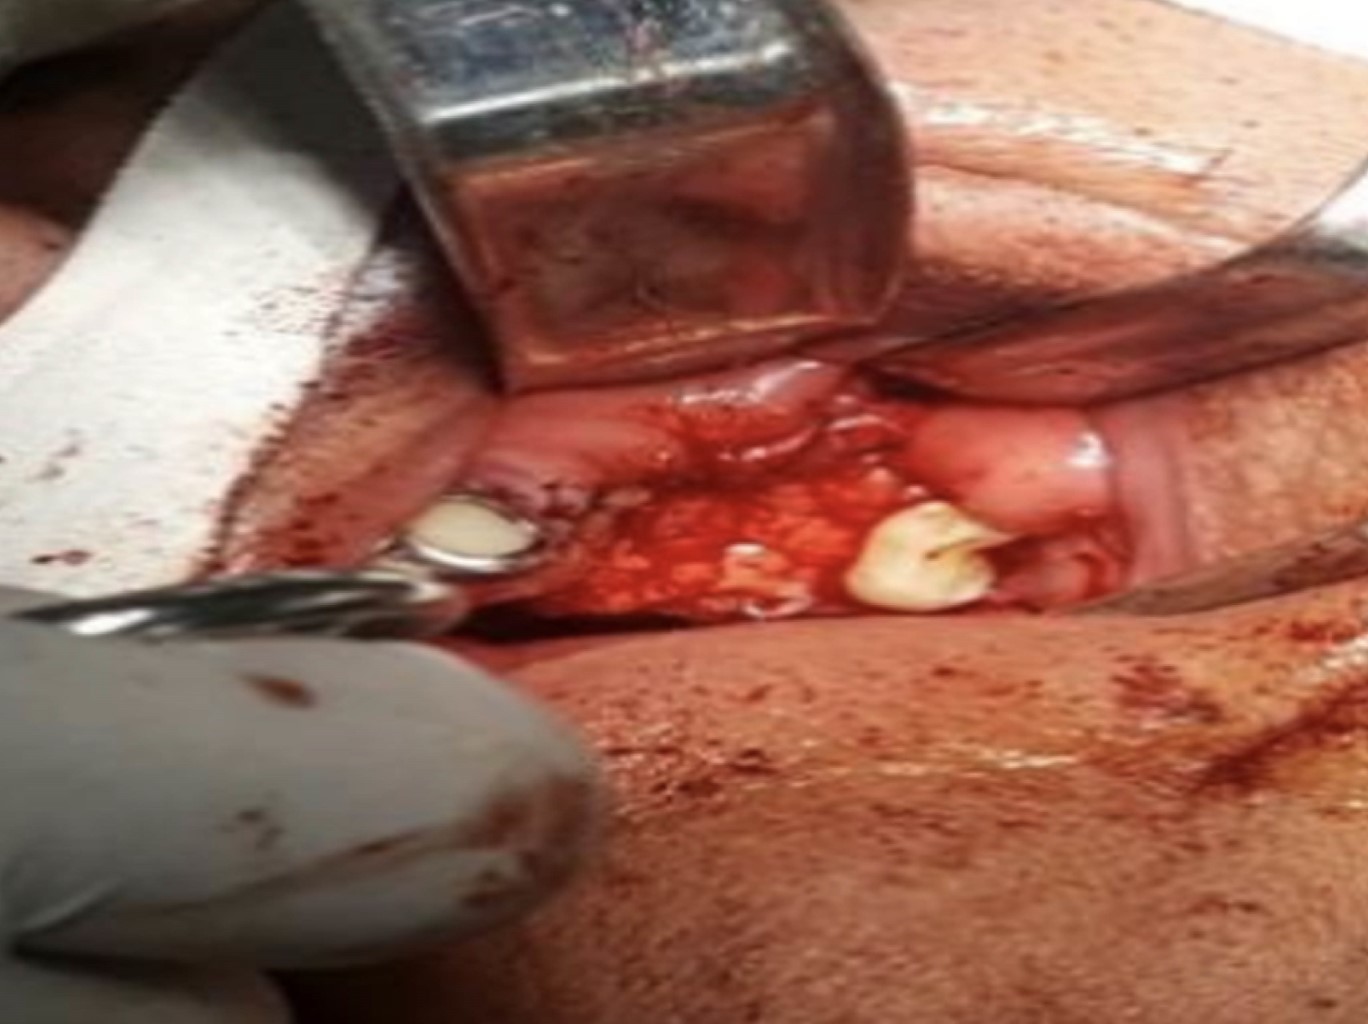

Para este procedimiento se utilizó sonda Bowman para medir el trayecto (Figura 2). Se realizó la disección de la BAB (Figura 3) y su avance hacia el defecto (Figura 4). Posteriormente se fijó el injerto (Figura 5) y se realizó la síntesis de los tejidos (Figura 6).

Figura 3